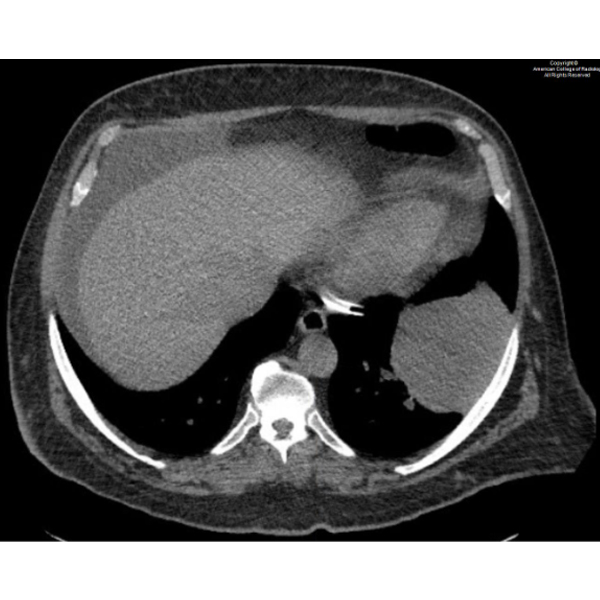

A 68-year-old male with no significant medical history presents for abdominal ultrasound.#ACRCaseinPoint

https://t.co/ZKGwIkx9MD